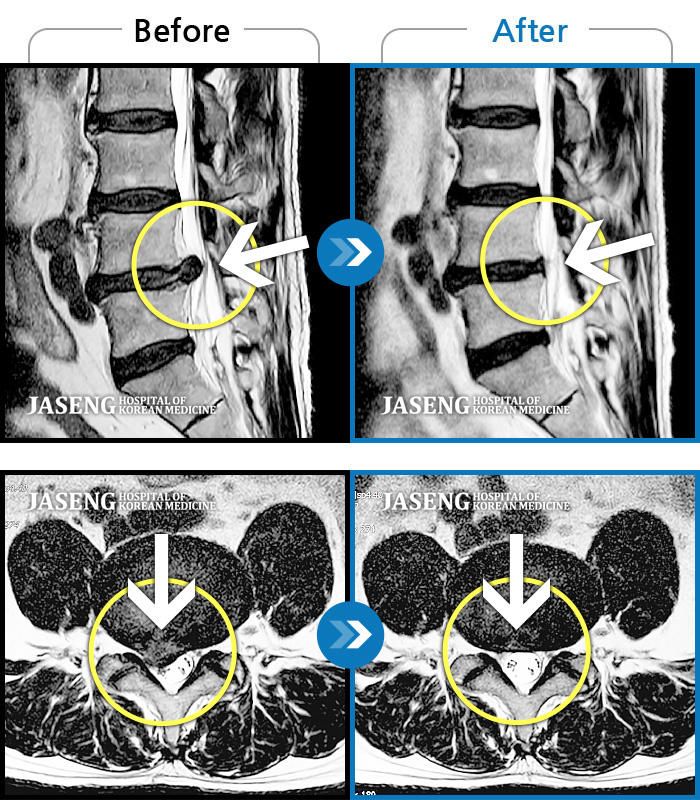

MRI ũ ʸ Ȯϼ.

[ؿ] 24.10.10~25.04.23